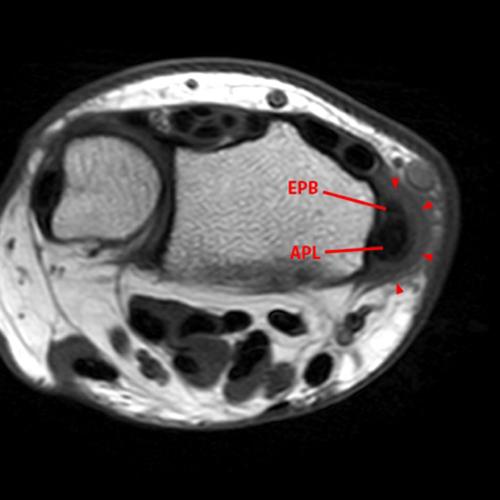

Figure 5. Axial fat-suppressed proton density-weighted image and contiguous sagittal T2-weighted images at the radial side of the wrist moving from ulnar (left) to radial (right) in the same patient as Figures 1 and 2. The EPB is small, which is a common variant. The APL has two slips with a larger main APL (APL 1) and a smaller accessory tendon (APL 2), although the initial interpretation was a tear. Useful clues in differentiating a tear from adjacent tendon slips are the length of the division, with slips tending to extend over a longer segment than tears, and identifying the distal insertions, which are often separate from the main APL tendon insertion. Here, the separate slip (APL 2) can be identified on the sagittal images proximal to the first extensor compartment and followed distally to insert on the abductor pollicis brevis muscle (APB).